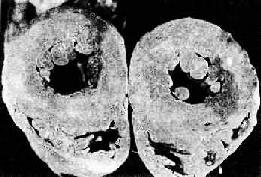

图8-11 高血压病时左心室向心性肥大(心脏横断面)

左心室壁增厚,乳头肌显著增粗